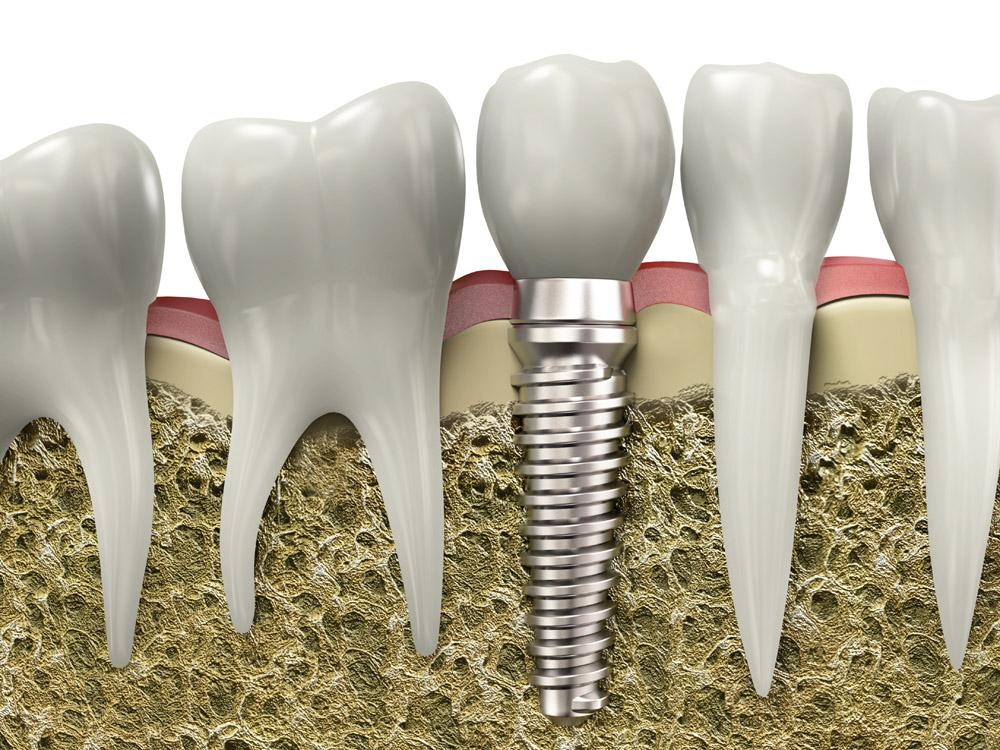

All-on-4/6種植是一項(xiàng)高深精密的手術(shù),對(duì)醫(yī)生技術(shù)、醫(yī)療設(shè)備的要求嚴(yán)格。因?yàn)榉N植牙上午種,下午就得受力,所以醫(yī)生需要辨別骨頭的質(zhì)量、密度,種進(jìn)去的每一顆植體擁有35牛的扭力,如果植體很松,戴上牙冠后便會(huì)搖晃,就意味著種植失敗,這是種植技術(shù)的難點(diǎn)之一。

另外,務(wù)必基臺(tái)與植體高度結(jié)合。很多地方?jīng)]辦法開(kāi)展種植牙技術(shù)的主要原因就在于此。